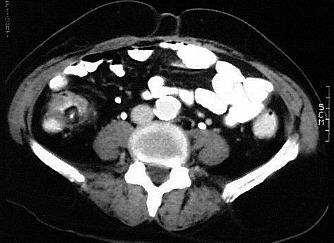

Abdominelles Aortenaneurysma

Aneurysmatische Erweiterungen der Aorta abdominalis sind nahezu ausschliesslich arteriosklerotischer Genese. Luetische, mykotische oder traumatische Formen sind selten. Zum überwiegenden Teil liegen die abdominellen Aneurysmen unterhalb der Nierenarterienabgänge (infrarenales Aortenaneurysma). Ein Übergang auf die Iliakalarterien ist häufig.

Pathologisch unterscheidet man das echte Aneurysma, das disseziierende Aneurysma mit Einriss der Intima und Einblutung in die Aortenwand und das Aneurysma spurium, welches einem abgekapselten Hämatom um die Aorta entspricht.

In der CT sollte die Untersuchung in einer frühen, arteriellen Kontrastmittelphase mit einer Scanverzögerung von ca. 25 Sekunden durchgeführt werden.

CT-morphologisch finden sich meist Verkalkungen der Aorta. Ab einem vergrösserten Aussendurchmesser der Aorta von über 4 cm oder nach distal zunehmendem Aortendurchmesser wird von einem Aneurysma ausgegangen. In vielen Fällen ist ein Teil des erweiterten Gefässlumens thrombosiert. Der Thrombus kann symmetrisch zirkulär oder sichelförmig der Gefässwand anliegen und lässt sich deutlich hypodens von dem kontrastierten Gefässlumen abgrenzen. Bei länger bestehender Erkrankung können Usuren an den angrenzenden Wirbelkörpern nachgewiesen werden.

Zum disseziierenden Aortenaneurysma kommt es durch Einriss der Intima mit Ausbildung eines intramuralen Hämatoms. Durch einen zusätzlichen weiter distal gelegenen Intimariss kann es zur Ausbildung eines zweiten durchströmten Lumens kommen. Es können dann ein echtes und falsches (intramurales) Lumen unterschieden werden, die computertomographisch kontrastmittelgefüllt dargestellt werden.

Ein rupturiertes Aortenaneurysma kann an einer Konturunschärfe der Gefässwand zum umgebenden Fettgewebe erkannt werden und führt zu oft ausgedehnten Blutungen in die Bauchhöhle. Teilweise kann das Leck anhand eines Kontrastmittelaustritts lokalisiert werden.

Verläuft der Blutaustritt langsam und chronisch, kann eine fibrotische Kapsel um das Hämatom entstehen, was zur Ausbildung eines Aneurysma spurium (Pseudoaneurysma) führt. Computertomographisch lässt im sich in diesem Bereich eine Unterbrechung der Aortenwandverkalkung nachweisen.